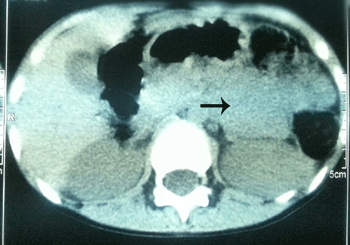

A 10-year-old girl presented with failure to thrive despite good appetite for 3 years. She also had a history of polyuria and polydipsia for one year. She was incidentally found to have a blood pressure of 170/110 mmHg. Her body weight was 21 kg (50th percentile for 7 years old), height was 128 cm (10th percentile), and her bone age was about 7 year. Her pulse was 120/min and rest of physical and systemic examinations were unremarkable. A 24-hour urine analysis revealed urine vanillylmandelic acid (VMA) of 25.4 mg/24hours (normal range, 0.4-0.6), metanephrine over 960 mcg/24hours (normal range, 0-350), and normetanephrine over 3840 mcg/24hours (normal range, 0-600). Her serum aldosterone and cortisol levels were normal. Other laboratory tests were within normal limits. Abdominal ultrasonography revealed solid heterogeneous mass with micro cysts, measuring 68 x 58 mm at the left adrenal region. CT scan of the abdomen showed a solid hetero-density mass lesion, measuring approximately 60 mm in diameter, near the upper pole of the left kidney (Fig. 1). Echocardiogram and ECG were unremarkable.

Figure 1: CT scan showing suprarenal mass (arrow). |